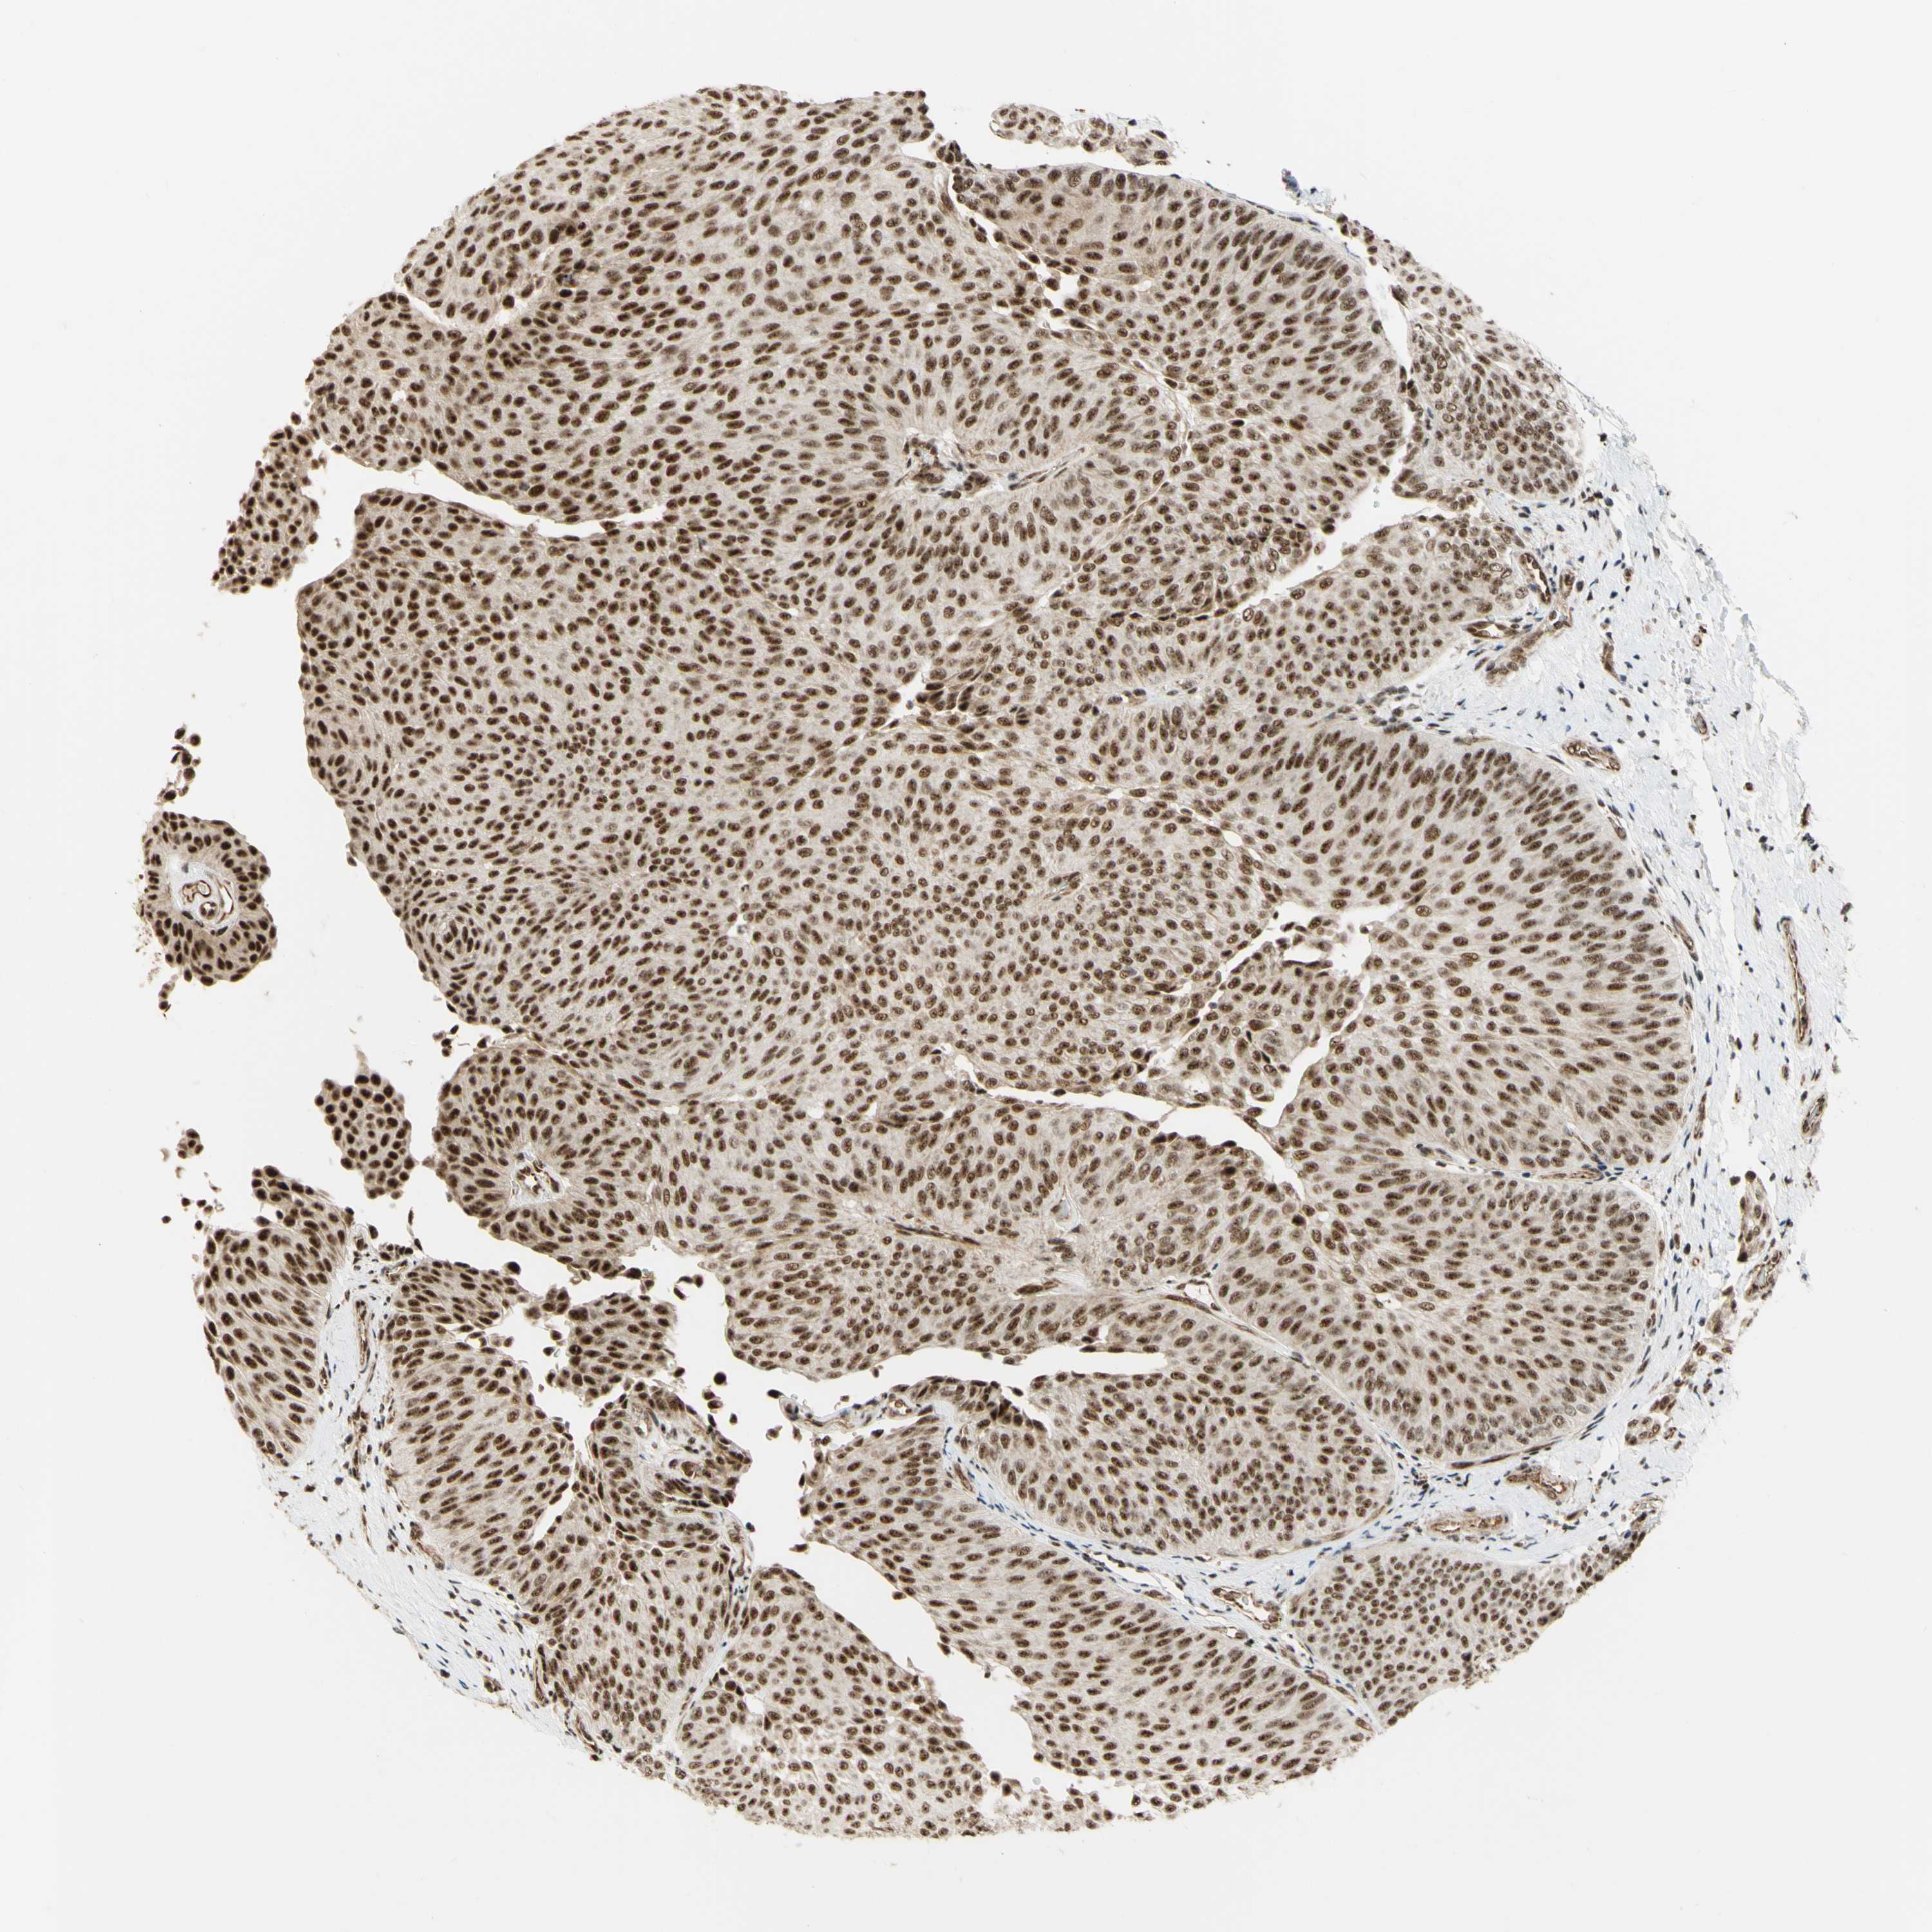

UROTHELIAL CANCER - Protein expressioni

A mouse-over function shows sample information and annotation data. Click on an image to view it in a full screen mode. Samples can be filtered based on level of antibody staining by selecting one or several of the following categories: high, medium, low and not detected. The assay and annotation is described here.

Antibody stainingi

Antibody staining in the annotated cell types in the current human tissue is reported as not detected, low, medium, or high, based on conventional immunohistochemistry profiling in selected tissues. This score is based on the combination of the staining intensity and fraction of stained cells.

Each image is clickable and will lead to virtual microscopy that enables deeper exploration of all samples and also displays staining intensity scores, fraction scores and subcellular localization as well as patient and tissue information for each sample.

Antibody HPA011352

Antibody CAB012273

Staining

High

Medium

Low

Not detected

Intensity

Strong

Moderate

Weak

Negative

Quantity

>75%

75%-25%

<25%

None

Location

Nuclear

Cytoplasmic/membranous

Cytoplasmic/membranous,nuclear

Urothelial carcinoma, Low grade

Urothelial carcinoma, High grade